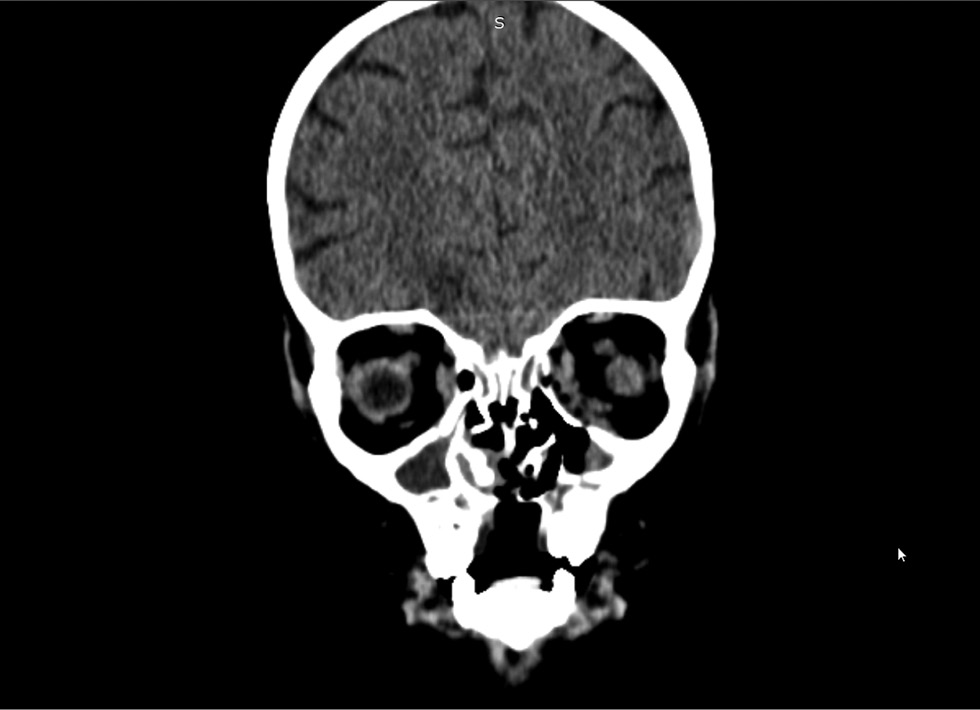

Рентгеновскую компьютерную томографию проводили в динамике на 36, 47, 63-й дни госпитализации. РКТ орбит и придаточных пазух носа выявила признаки множественных обширных очагов деструкции медиальных стенок орбит, костей носовой полости, твёрдого нёба, альвеолярных отростков верхнечелюстной кости, дефект мягкого нёба (рис. 4, 5). С помощью магнитно-резонансной томографии орбит, придаточных пазух носа, головного мозга на 63-й день госпитализации обнаружены признаки множественных обширных очагов деструкции медиальных стенок орбит, костей носовой полости, твёрдого нёба, альвеолярных отростков верхнечелюстной кости, дефект мягкого нёба (рис. 6, 7).

Рис. 4. Рентгеновская компьютерная томография орбит, придаточных пазух носа, головного мозга на 36-й день госпитализации.

Fig. 4. X-ray computed tomography of the orbits, paranasal sinuses, and brain on day 36 of hospitalization.

Рис. 5. Рентгеновская компьютерная томография орбит, придаточных пазух носа, головного мозга на 47-й день госпитализации.

Fig. 5. X-ray computed tomography of the orbits, paranasal sinuses, and brain on the day 47 of hospitalization.